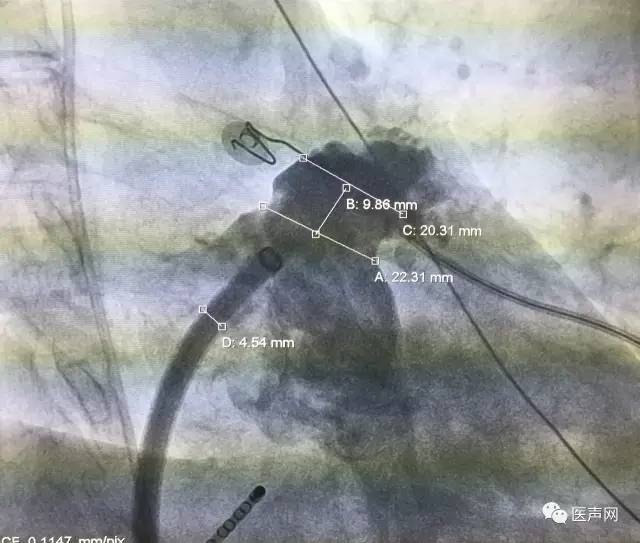

左心耳造影